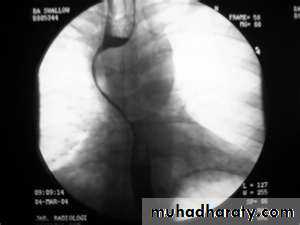

PULSION DIVERTICULUM

Due to:raised intra-luminal tension

Chocking after meal .

In cervical portion at level of C5

Posteriorly (Killience dehiscent)

Lateral view show increased pre-vertebral space with air fluid level.

Confirmed by Ba. Swallow.

TRACTION DIVERTICULUM

Out pouching of lumen laterally due to fibrosis & adhesions ( post-Tb.)

In the middle third at level of hilum

Up ward direction of diverticulum

Irregular base

On the far left a traction diverticulum (arrow) due to hilar granulomatous disease. Calcified adenopathy (asterisk).

In the middle a pulsion diverticulum (arrow) due to high intra luminal pressure.

On the right multiple pulsion diverticula (arrows)